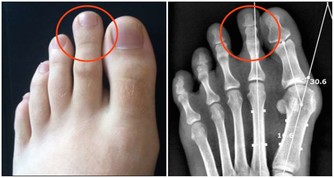

膝關節

膝關節可以說是退化性關節炎的最大宗。關節就如同車子的輪胎般,如果常煞車、摩擦多,輪胎就會提早報銷。門診中患者常見的主述症狀如下:

⑴疼痛加上軟痠及卡住的感覺,多屬半月軟骨的問題。

⑵下樓梯時膝蓋痠軟,多屬髕骨軟化,以女性居多。

⑶從坐姿站起時兩腿感到痠軟,通常屬於骨小樑退化。

⑷關節感到卡卡的,且無法伸直或彎曲,則是半月板破裂。